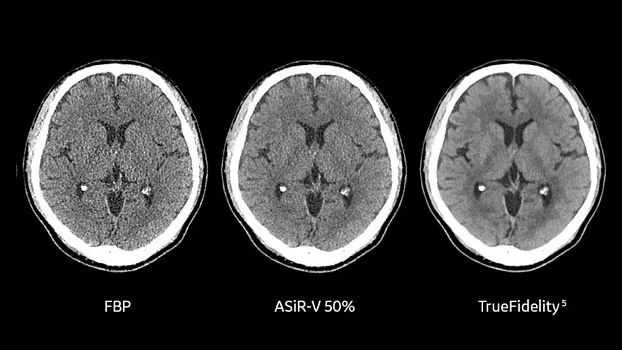

Технология TrueFidelity

Revolution Ascend поддерживает технологию TrueFidelity**, которая реконструирует изображения с помощью алгоритмов глубокого обучения. Она обеспечивает глубокую детализацию, естественную текстуру, высокую контрастность и четкость изображений. TrueFidelity генерирует изображения с помощью алгоритмов искусственного интеллекта. Это позволяет, с одной стороны, использовать низкую лучевую нагрузку, как при итеративной реконструкции, а с другой стороны, получать изображения, не уступающие по качеству методу фильтрованных обратных проекций.